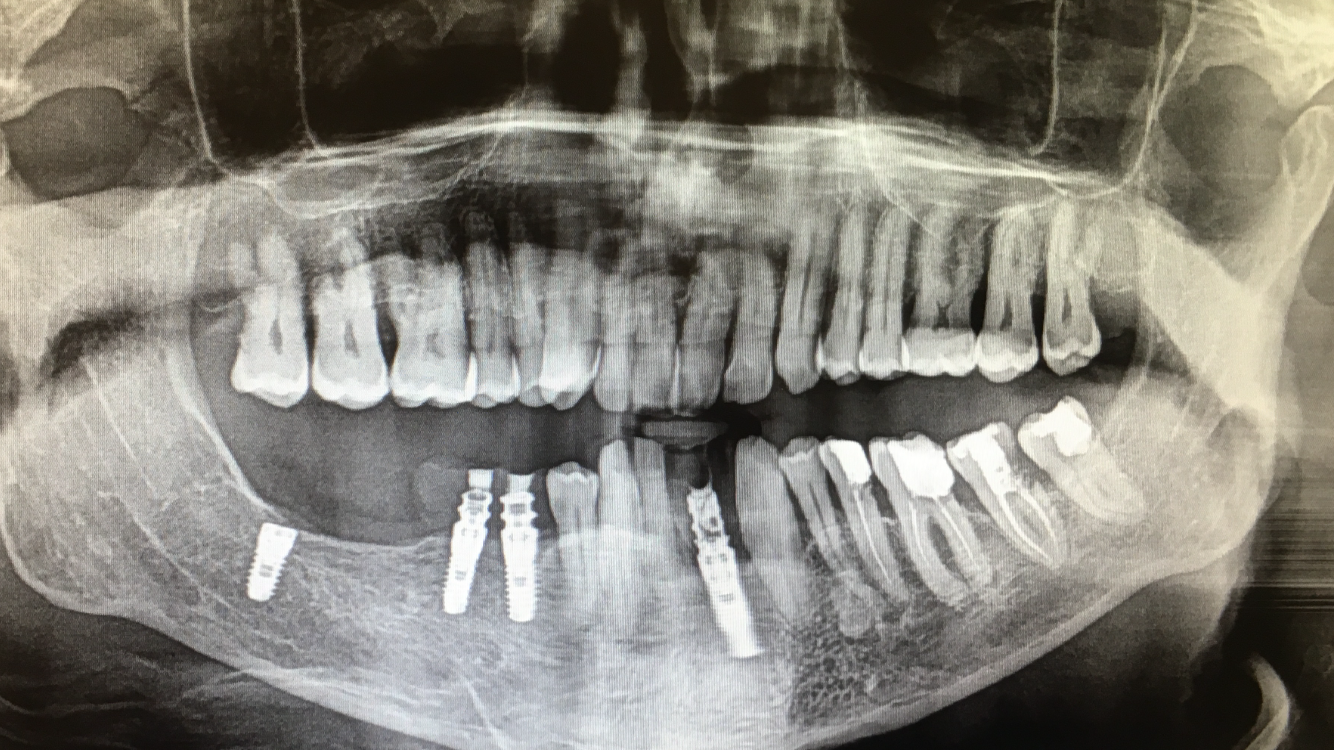

Duda marca y diámetro de implantes en sector anterior.

Paciente de origen colombiano que acude a consulta con 4 implantes colocados en sector anterosuperior en posiciones #12, #11,#21 y #22. Necesitamos conocer la marca y diámetro de los implantes [...]